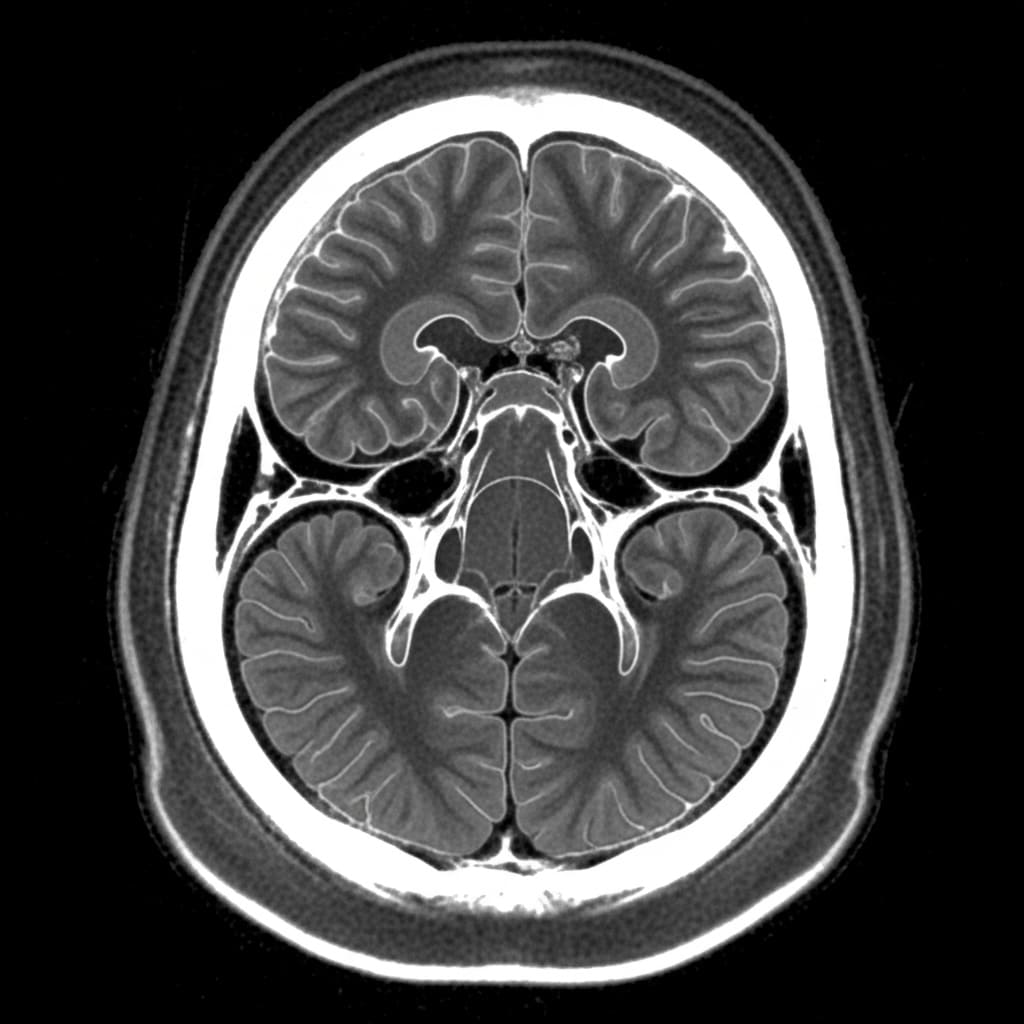

특히 신경외과는 CT, MRI 같은 영상 검사로 구조적 문제를 확인한 뒤 수술 여부를 판단한다. 최근에는 최소 침습 수술, 내시경 수술 등 첨단 기술이 적용되는 경우도 많다.